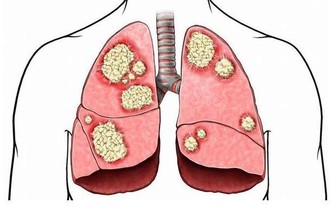

腸胃病科首席醫療顧問表示,大腸癌是我國第二癌症殺手,而華人則是患上大腸癌的最大群體。

大腸癌的早期有四大症狀